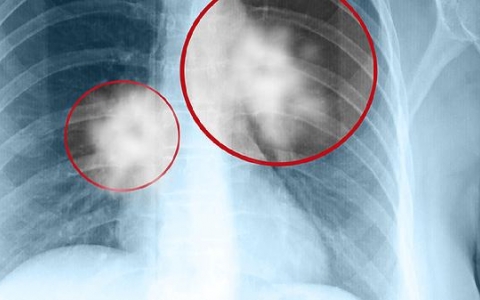

肺结节ct拍片能看出来吗

肺结节通过CT拍片通常是可以看到的。CT检查是一种常见的影像学方法,能够帮助医生识别肺部的异常情况。如果在检查中发现了肺结节,建议尽快就医,并在专业医生的指导下

肺结节a高危什么意思啊

肺结节A高危通常指的是在影像学检查中发现肺部有结节,并且这个结节被评估为有较高的恶性可能性。听到这样的诊断,可能让人心里咯噔一下,但别急,及时就医是关键。医生会

肺结节按密度怎么分类的

肺结节的密度分类主要可以分为实性结节、部分实性结节和磨玻璃样结节。这些结节在影像学上呈现出不同的特征。了解这些差异有助于我们更好地判断结节的性质以及可能的健康风